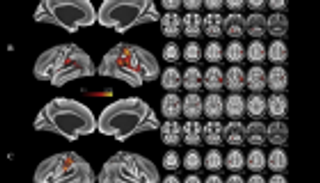

ونجحوا، بعد دراسات على فئران التجارب، في تكرار ديناميات كاملة من الخلايا العصبية لمنطقة الحصين والخلايا التنفسية، في إطار مجموعة واسعة من المحفزات.